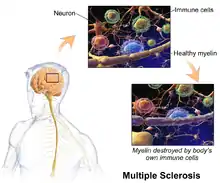

| Multiple sclerosis | |

Multiple sclerosis (MS) is an autoimmune disease in which the insulating covers of nerve cells in the brain and spinal cord are damaged.[3] This damage disrupts the ability of parts of the nervous system to transmit signals, resulting in a range of signs and symptoms, including physical, mental, and sometimes psychiatric problems.[1][8][9] Specific symptoms can include double vision, vision loss, eye pain, muscle weakness, and loss of sensation or coordination.[3][10][11] MS takes several forms, with new symptoms either occurring in isolated attacks (relapsing forms) or building up over time (progressive forms).[12][13] In the relapsing forms of MS, between attacks, symptoms may disappear completely, although some permanent neurological problems often remain, especially as the disease advances.[13] In the progressive forms of MS, bodily function slowly deteriorates and disability worsens once symptoms manifest and will steadily continue to do so if the disease is left untreated.[14]

While the cause is unclear, the underlying mechanism is thought to be either destruction by the immune system or failure of the myelin-producing cells.[4] Proposed causes for this include immune dysregulation, genetics, and environmental factors, such as viral infections.[15][16][8][17] MS is usually diagnosed based on the presenting signs and symptoms and the results of supporting medical tests.[5]

Pathophysiology

The three main characteristics of MS are the formation of lesions in the central nervous system (also called plaques), inflammation, and the destruction of myelin sheaths of neurons. These features interact in a complex and not yet fully understood manner to produce the breakdown of nerve tissue, and in turn, the signs and symptoms of the disease.[1] MS is believed to be an immune-mediated disorder that develops from an interaction of the individual's genetics and as yet unidentified environmental causes.[8] Damage is believed to be caused, at least in part, by attack on the nervous system by a person's own immune system.[1]

To be specific, MS involves the loss of oligodendrocytes, the cells responsible for creating and maintaining a fatty layer—known as the myelin sheath—which helps the neurons carry electrical signals (action potentials).[1] This results in a thinning or complete loss of myelin, and as the disease advances, the breakdown of the axons of neurons. When the myelin is lost, a neuron can no longer effectively conduct electrical signals.[8] A repair process, called remyelination, takes place in early phases of the disease, but the oligodendrocytes are unable to completely rebuild the cell's myelin sheath.[74] Repeated attacks lead to successively less effective remyelinations, until a scar-like plaque is built up around the damaged axons.[74] These scars are the origin of the symptoms and during an attack magnetic resonance imaging (MRI) often shows more than 10 new plaques.[1] This could indicate that some number of lesions exist, below which the brain is capable of repairing itself without producing noticeable consequences.[1] Another process involved in the creation of lesions is an abnormal increase in the number of astrocytes due to the destruction of nearby neurons.[1] A number of lesion patterns have been described.[75]

Inflammation

Apart from demyelination, the other sign of the disease is inflammation. Fitting with an immunological explanation, the inflammatory process is caused by T cells, a kind of lymphocytes that plays an important role in the body's defenses.[8] T cells gain entry into the brain as a result of disruptions in the blood–brain barrier. The T cells recognize myelin as foreign and attack it, explaining why these cells are also called "autoreactive lymphocytes".[1]

The attack on myelin starts inflammatory processes, which trigger other immune cells and the release of soluble factors like cytokines and antibodies. A further breakdown of the blood-brain barrier, in turn, causes a number of other damaging effects, such as swelling, activation of macrophages, and more activation of cytokines and other destructive proteins.[8] Inflammation can potentially reduce transmission of information between neurons in at least three ways.[1] The soluble factors released might stop neurotransmission by intact neurons. These factors could lead to or enhance the loss of myelin, or they may cause the axon to break down completely.[1]